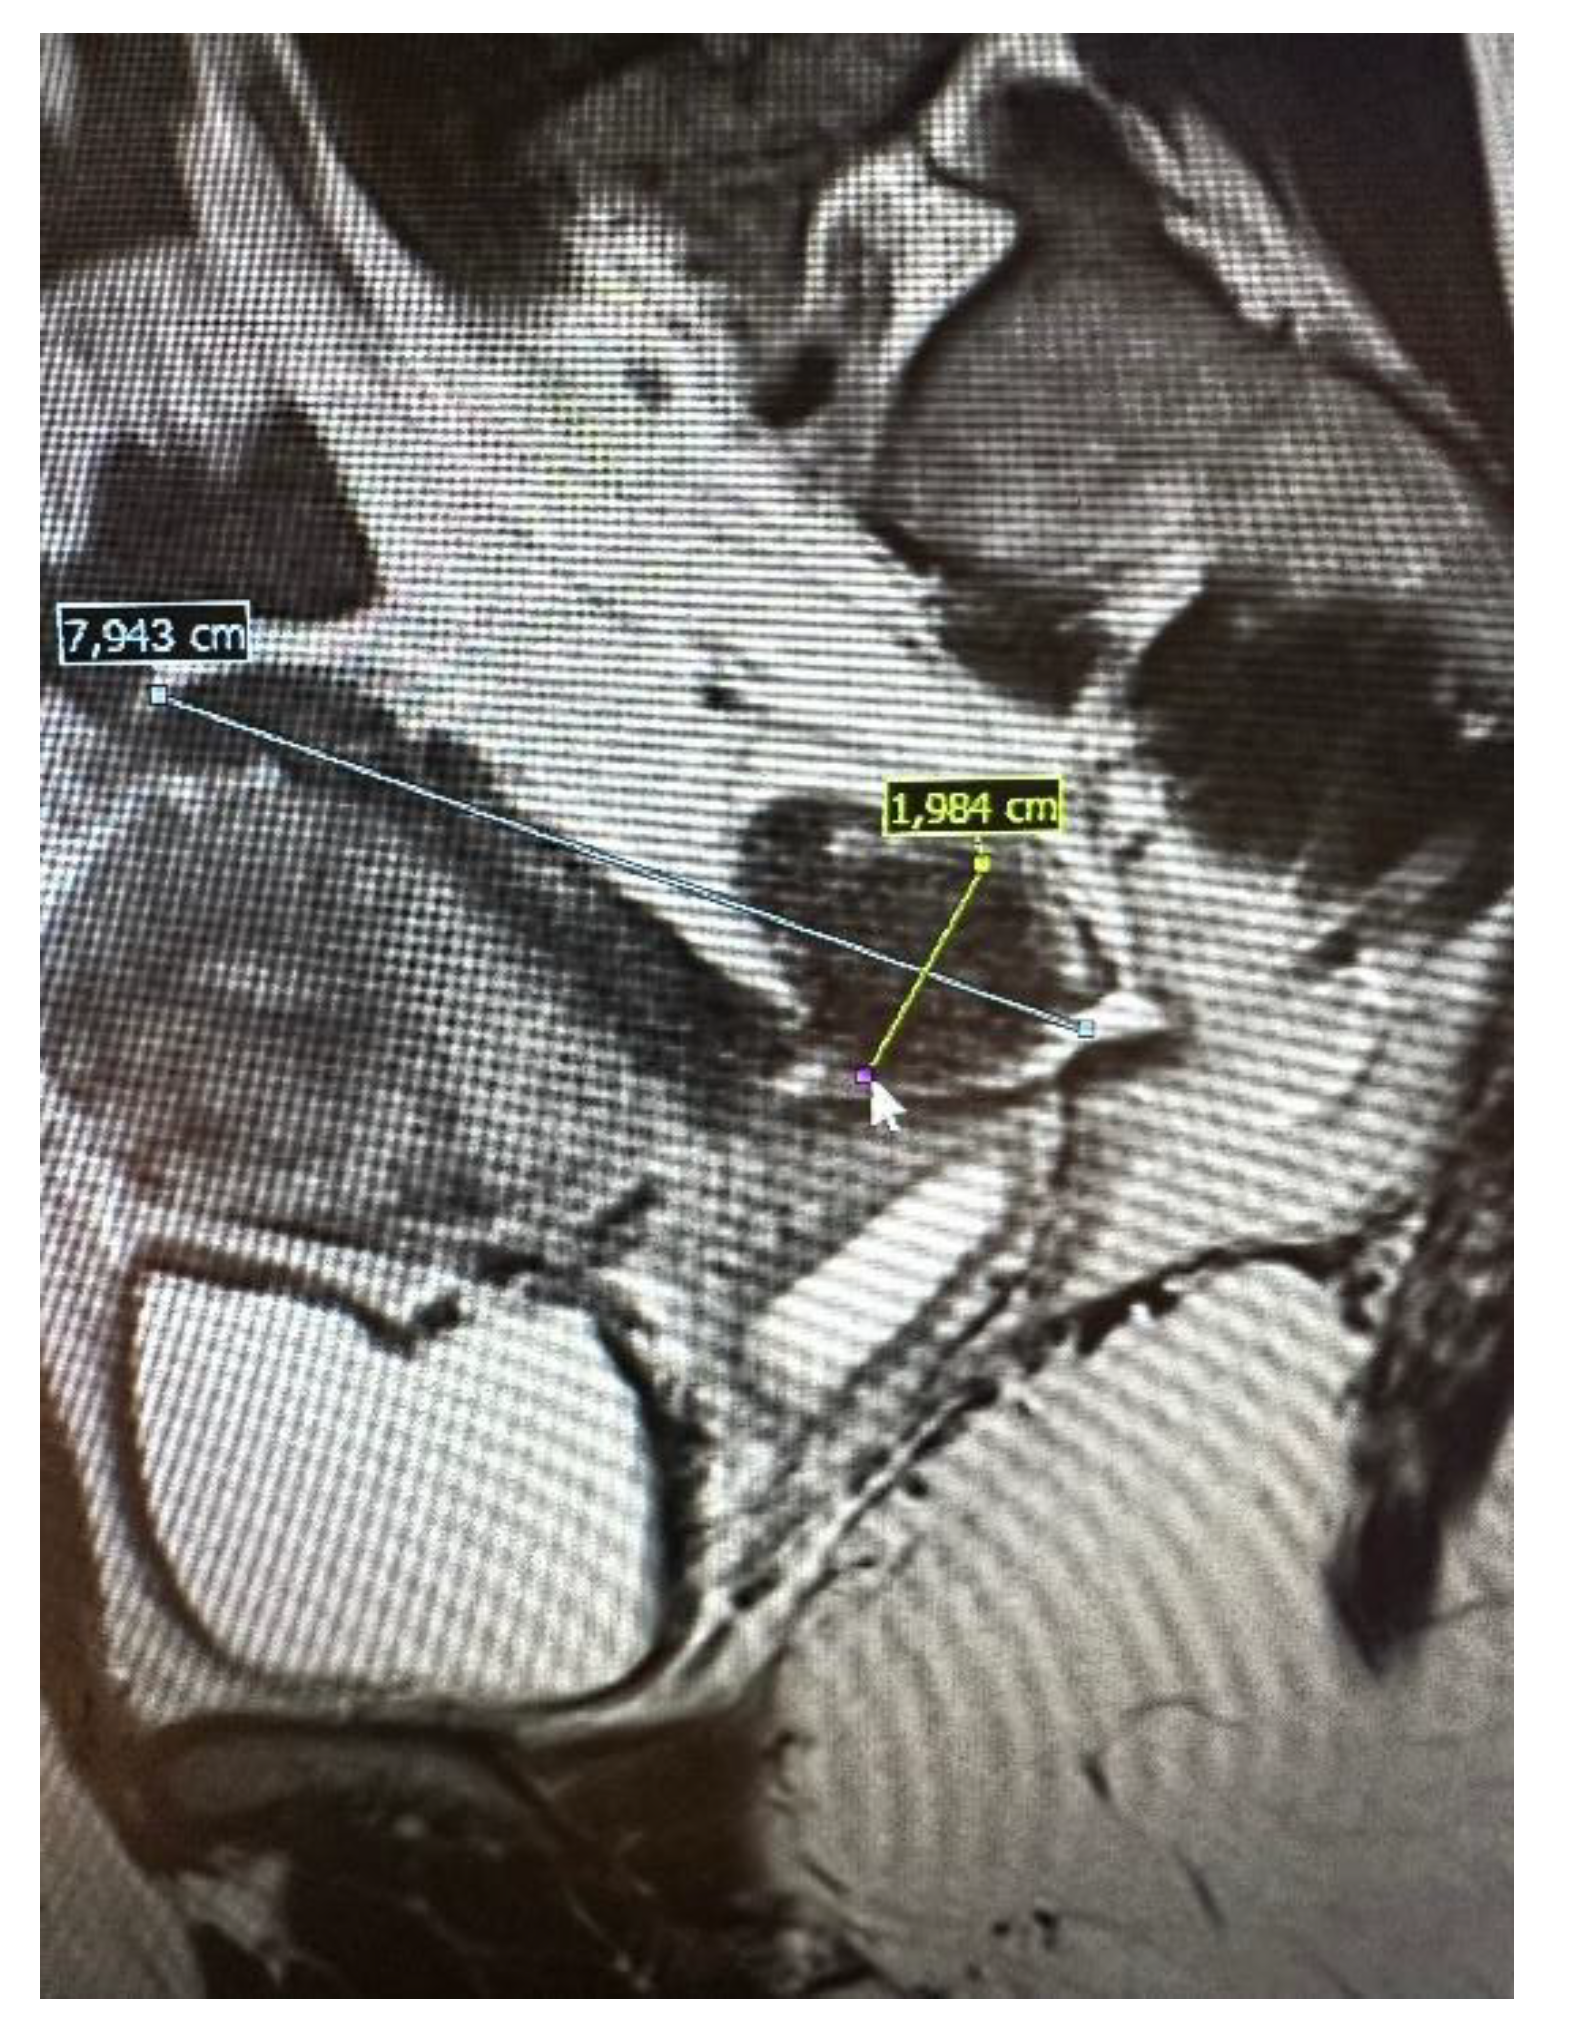

All patients underwent preoperative ultrasound examination by an expert surgeon-gynecologist – (E.M.-N.), with detailed pelvic compartments assessment via transvaginal sonography (TVS) and with kidney congestion assessment via transabdominal sonography (TAS), following an adapted protocol based on IDEA group guidelines. [7] Examinations were performed on Voluson E8 Expert with the use of vaginal probe RIC5-9-D (depth max 16 cm) and abdominal probe RAB2-5-D. Detailed report was recorded for each patient. Examples of ultrasound examination images are shown in Figure 1.

Figure 1. Preoperative ultrasound examination: the bowel DE nodule ( TVS exam), congestion in the left kidney (TAS exam).

Figure 2. Preoperative magnetic resonance examination. The same bowel DE nodule as presented in TVS above (compare Figure 1).